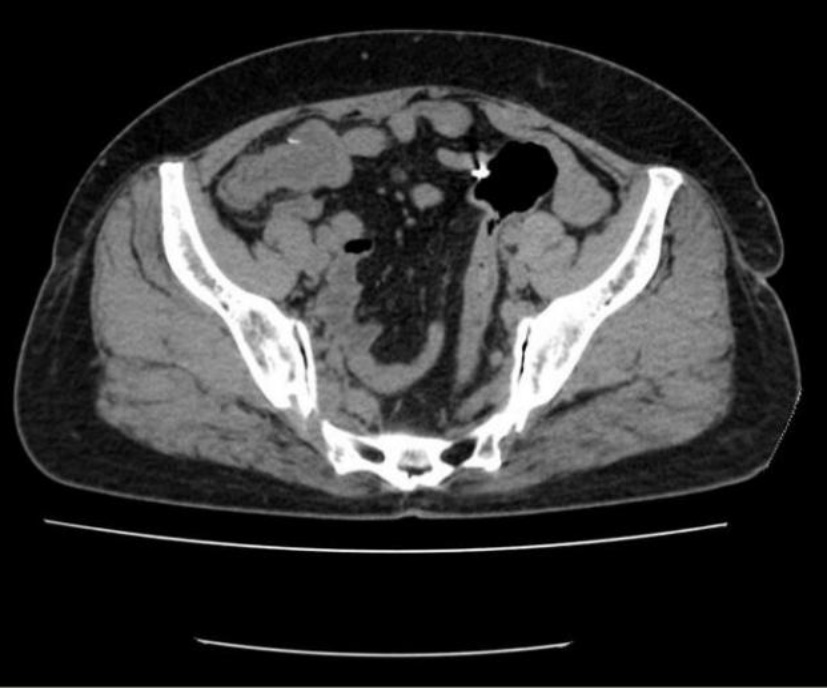

患者,女,56岁。2024年3月因“间断右下腹痛1月余”就医。患者1月余前无明显诱因开始出现右下腹痛,呈阵发性钝痛,无恶心、呕吐,无腹胀、腹泻,无畏寒、发热,无呕血、黑便,行B超示:右下腹阑尾区不均质低回声团,阑尾炎可能性大,给予对症抗感染治疗,症状有所缓解,但仍反复疼痛,为求进一步治疗收入当地医院。既往有高血压病史,16年前因肠套叠行结肠切除手术。查体:心肺检查未见明显异常,腹部平坦,无腹壁静脉曲张,腹部可见陈旧手术瘢痕,腹软,右下腹压痛,无反跳痛及肌紧张,腹部未触及明显肿块,叩诊呈清音,移动性浊音阴性,肠鸣音3次/分,未闻及血管杂音。入院后完善血常规:白细胞6.61*10^9/L (3.5~9.5)、消化系统肿瘤标记物:癌胚抗原2.4 ng/ml (13~150),甲胎蛋白3.87 ng/ml (≤7),类抗原19-9 31.9 ng/ml (≤34)均正常。腹部CT示:腹腔内部分小肠积液。右下腹局部见管状影,壁钙化。回盲部见多发微小结节,乙状结肠内见高密度灶(见图1(a)~(d))。肠镜示:回盲瓣呈唇状,阑尾肿大,开口处黏膜粗糙糜烂,蠕动可(见图2)。给予行腹腔镜下阑尾切除术,术中探查见:阑尾端侧与临近小肠致密黏连,无法分离,完整切除阑尾困难,为避免损伤黏连小肠,剪刀贴近黏连处将阑尾浆膜剪开,剥离阑尾,部分浆膜残留于小肠,距离阑尾根部0.5 cm结扎,切除阑尾。术后病理:送检破碎阑尾组织,部分管腔上皮呈高级别上皮内瘤变,少量破碎游离组织内见数个异型腺体浸润性生长,考虑癌变,高分化腺癌。组织碎,浸润层次不明确,阑尾肌层及浆膜层见多量无细胞黏液及炎症反应(见图3(a)图3(b))。患者术后5天顺利出院。

(a) (b)

(c) (d)

Figure 1. Abdominal CT (Before the first surgery)

1. 腹部CT(第一次手术前)